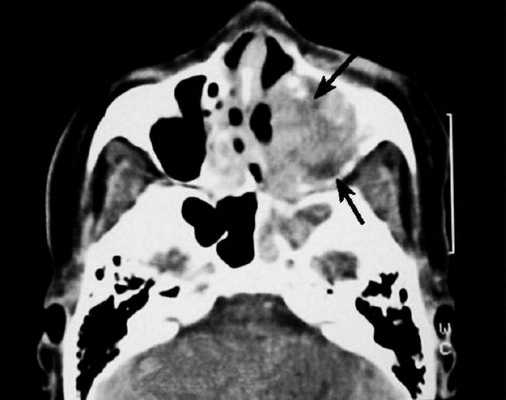

Слева — КТ-снимок одонтогенной кисты в верхнечелюстном синусе, справа — МР-фото образования (указано стрелкой) в гайморовой пазухе